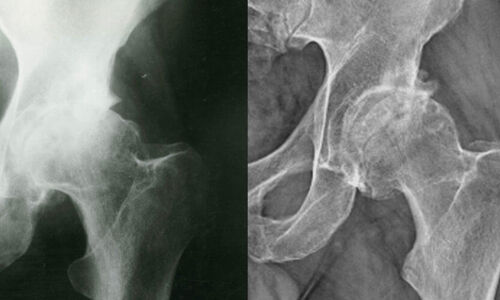

ന്യൂഡല്ഹി: ഡല്ഹി ബിഎല്കെ സൂപ്പര് സ്പെഷ്യല് ആശുപത്രിയില് പ്രവേശിപ്പിക്കപ്പെട്ട മൂന്ന് പേരില് കൊവിഡ് രോഗമുക്തരെ ബാധിക്കുന്ന ഗുരുതരമായ എല്ല് രോഗം കണ്ടെത്തി. 32 നും 40നും ഇടയിലുള്ള ഈ രോഗികളില് ഒരാളെ ശസ്ത്രക്രിയക്ക് വിധേയനാക്കിയിട്ടുണ്ട്.

അവാസ്കുലര് നെക്രോസിസ് അഥവാ എവിഎന് എന്ന പേരില് അറിയപ്പെടുന്ന ഈ എല്ലു രോഗം അമിതമായി സ്റ്റിറോയ്ഡ് കലര്ന്ന മരുന്നുകള് ഉപയോഗിച്ച് കൊവിഡ് രോഗത്തിന് ചികില്സ തേടിയവരിലാണ് കണ്ടുവരുന്നത്. ഈ രോഗം ബാധിച്ചവരില് രക്തചംക്രമണം കുറയുന്നതിന്റെ ഭാഗമായി എല്ലിന്റെ കോശങ്ങള് നശിച്ചുപോകുന്നു. എല്ലില് പൊട്ടലുകള്ക്ക് ഇത് കാരണമാവും. സന്ധികളില് എല്ലുകള് സ്ഥാനം തെറ്റാനും പൊട്ടാനും തുടങ്ങും.

കൊവിഡാനന്തര ഗുരുതരരോഗമായാണ് ഇത് കണക്കാക്കുന്നത്.

സ്റ്റിറോയ്ഡ് ഉപയോഗിച്ച് ഉടനെ ഈ ഫലം കാണണമെന്നില്ല. മൂന്ന് മുതല് ഒരു വര്ഷം വരെ സമയമെടുത്താണ് രോഗബാധ ദൃശ്യമാവുക.